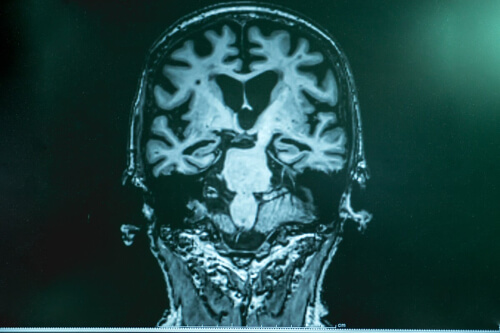

Jak wspomnieliśmy na początku, nie poznano jeszcze w pełni pochodzenia choroby Alzheimera. Zidentyfikowano jednak pewne patofizjologiczne zmiany charakterystyczne dla tej choroby. Chodzi na przykład o złogi białka amyloidu beta, które ostatecznie tworzą blaszki wokół neuronów i czynią je bezużytecznymi.

Otóż jak zbadano, aktywność gamma mózgu pacjentów z chorobą Alzheimera najwyraźniej ulega pogorszeniu. Może się to przyczyniać się do deficytów w złożonych funkcjach poznawczych, takich jak wspomniane powyżej.